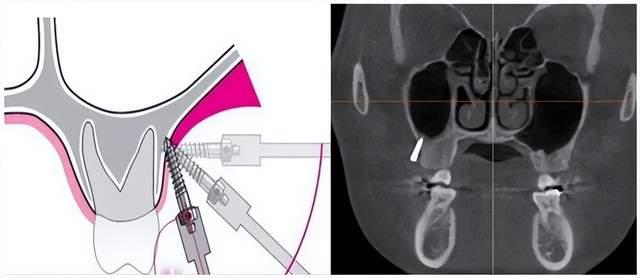

颧牙槽嵴支抗钉的植入

颧牙槽嵴部位

从膜龈联合处或其牙合方植入,大约距离牙槽嵴顶5~6mm的位置

颧牙槽嵴微种植体的适应证还有:在上颌拔牙病例中作为内收前牙的支抗